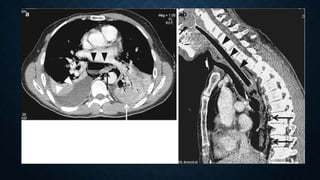

Tension haemopneumothorax. Axial contrast-

enhanced CT at mediastinal window shows a

right tension haemopneumothorax with

heterogeneous increased density due to

presence of blood clots and a significant shift

of the mediastinum contralaterally.

Tension pneumothorax. Sagittal reformatted CT image

at lung window showing tension pneumothorax with

significantly collapsed lung at the posterior part of the

hemithorax associated with ipsilateral pleural effusion.